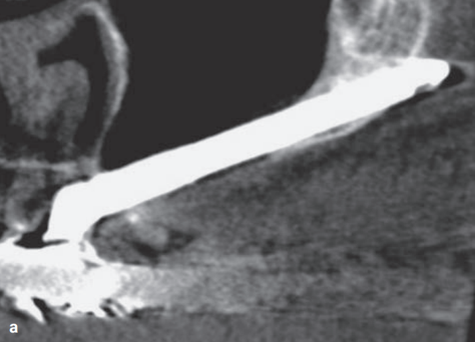

ZAGA 3

•Передняя стенка верхней челюсти очень вогнутая.

•Шейка имплантата расположена на альвеолярном гребне.

•Большая часть тела имплантата имеет передний экстрасинусальный путь.

•Средняя часть тела имплантата не касается самой вогнутой части стенки.

•Имплантат контактирует с костью в корональной альвеолярной и апикальной скуловой кости.

Эта группа составила 9% пациентов.